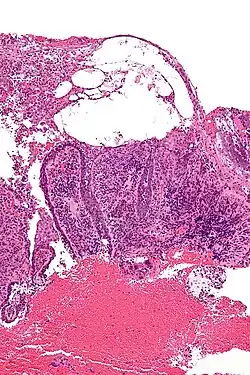

| Micrograph of pemphigus vulgaris with the characteristic "tombstoning". H&E stain. | |

Pemphigus is an autoimmune disease caused by antibodies directed against both desmoglein 1 and desmoglein 3 present in desmosomes. Loss of desmosomes results in loss of cohesion between keratinocytes in the epidermis, and a disruption of the barrier function served by intact skin. The process is classified as a type II hypersensitivity reaction (in which antibodies bind to antigens on the body's own tissues). On histology, the basal keratinocytes are usually still attached to the basement membrane leading to a characteristic appearance called "tombstoning". Transudative fluid accumulates in between the keratinocytes and the basal layer (suprabasal split), forming a blister that is easily dislodged when a lateral force is applied, resulting in what is known as a positive Nikolsky's sign.[6] This is a contrasting feature from bullous pemphigoid, which is thought to be due to anti-hemidesmosome antibodies, and where the detachment occurs between the epidermis and dermis (subepidermal bullae). Clinically, pemphigus vulgaris is characterized by extensive flaccid blisters and mucocutaneous erosions. The severity of the disease, as well as the mucosal lesions, is believed to be directly proportional to the levels of desmoglein 3. Milder forms of pemphigus (like foliacious and erythematoses) are more anti-desmoglein 1 heavy.